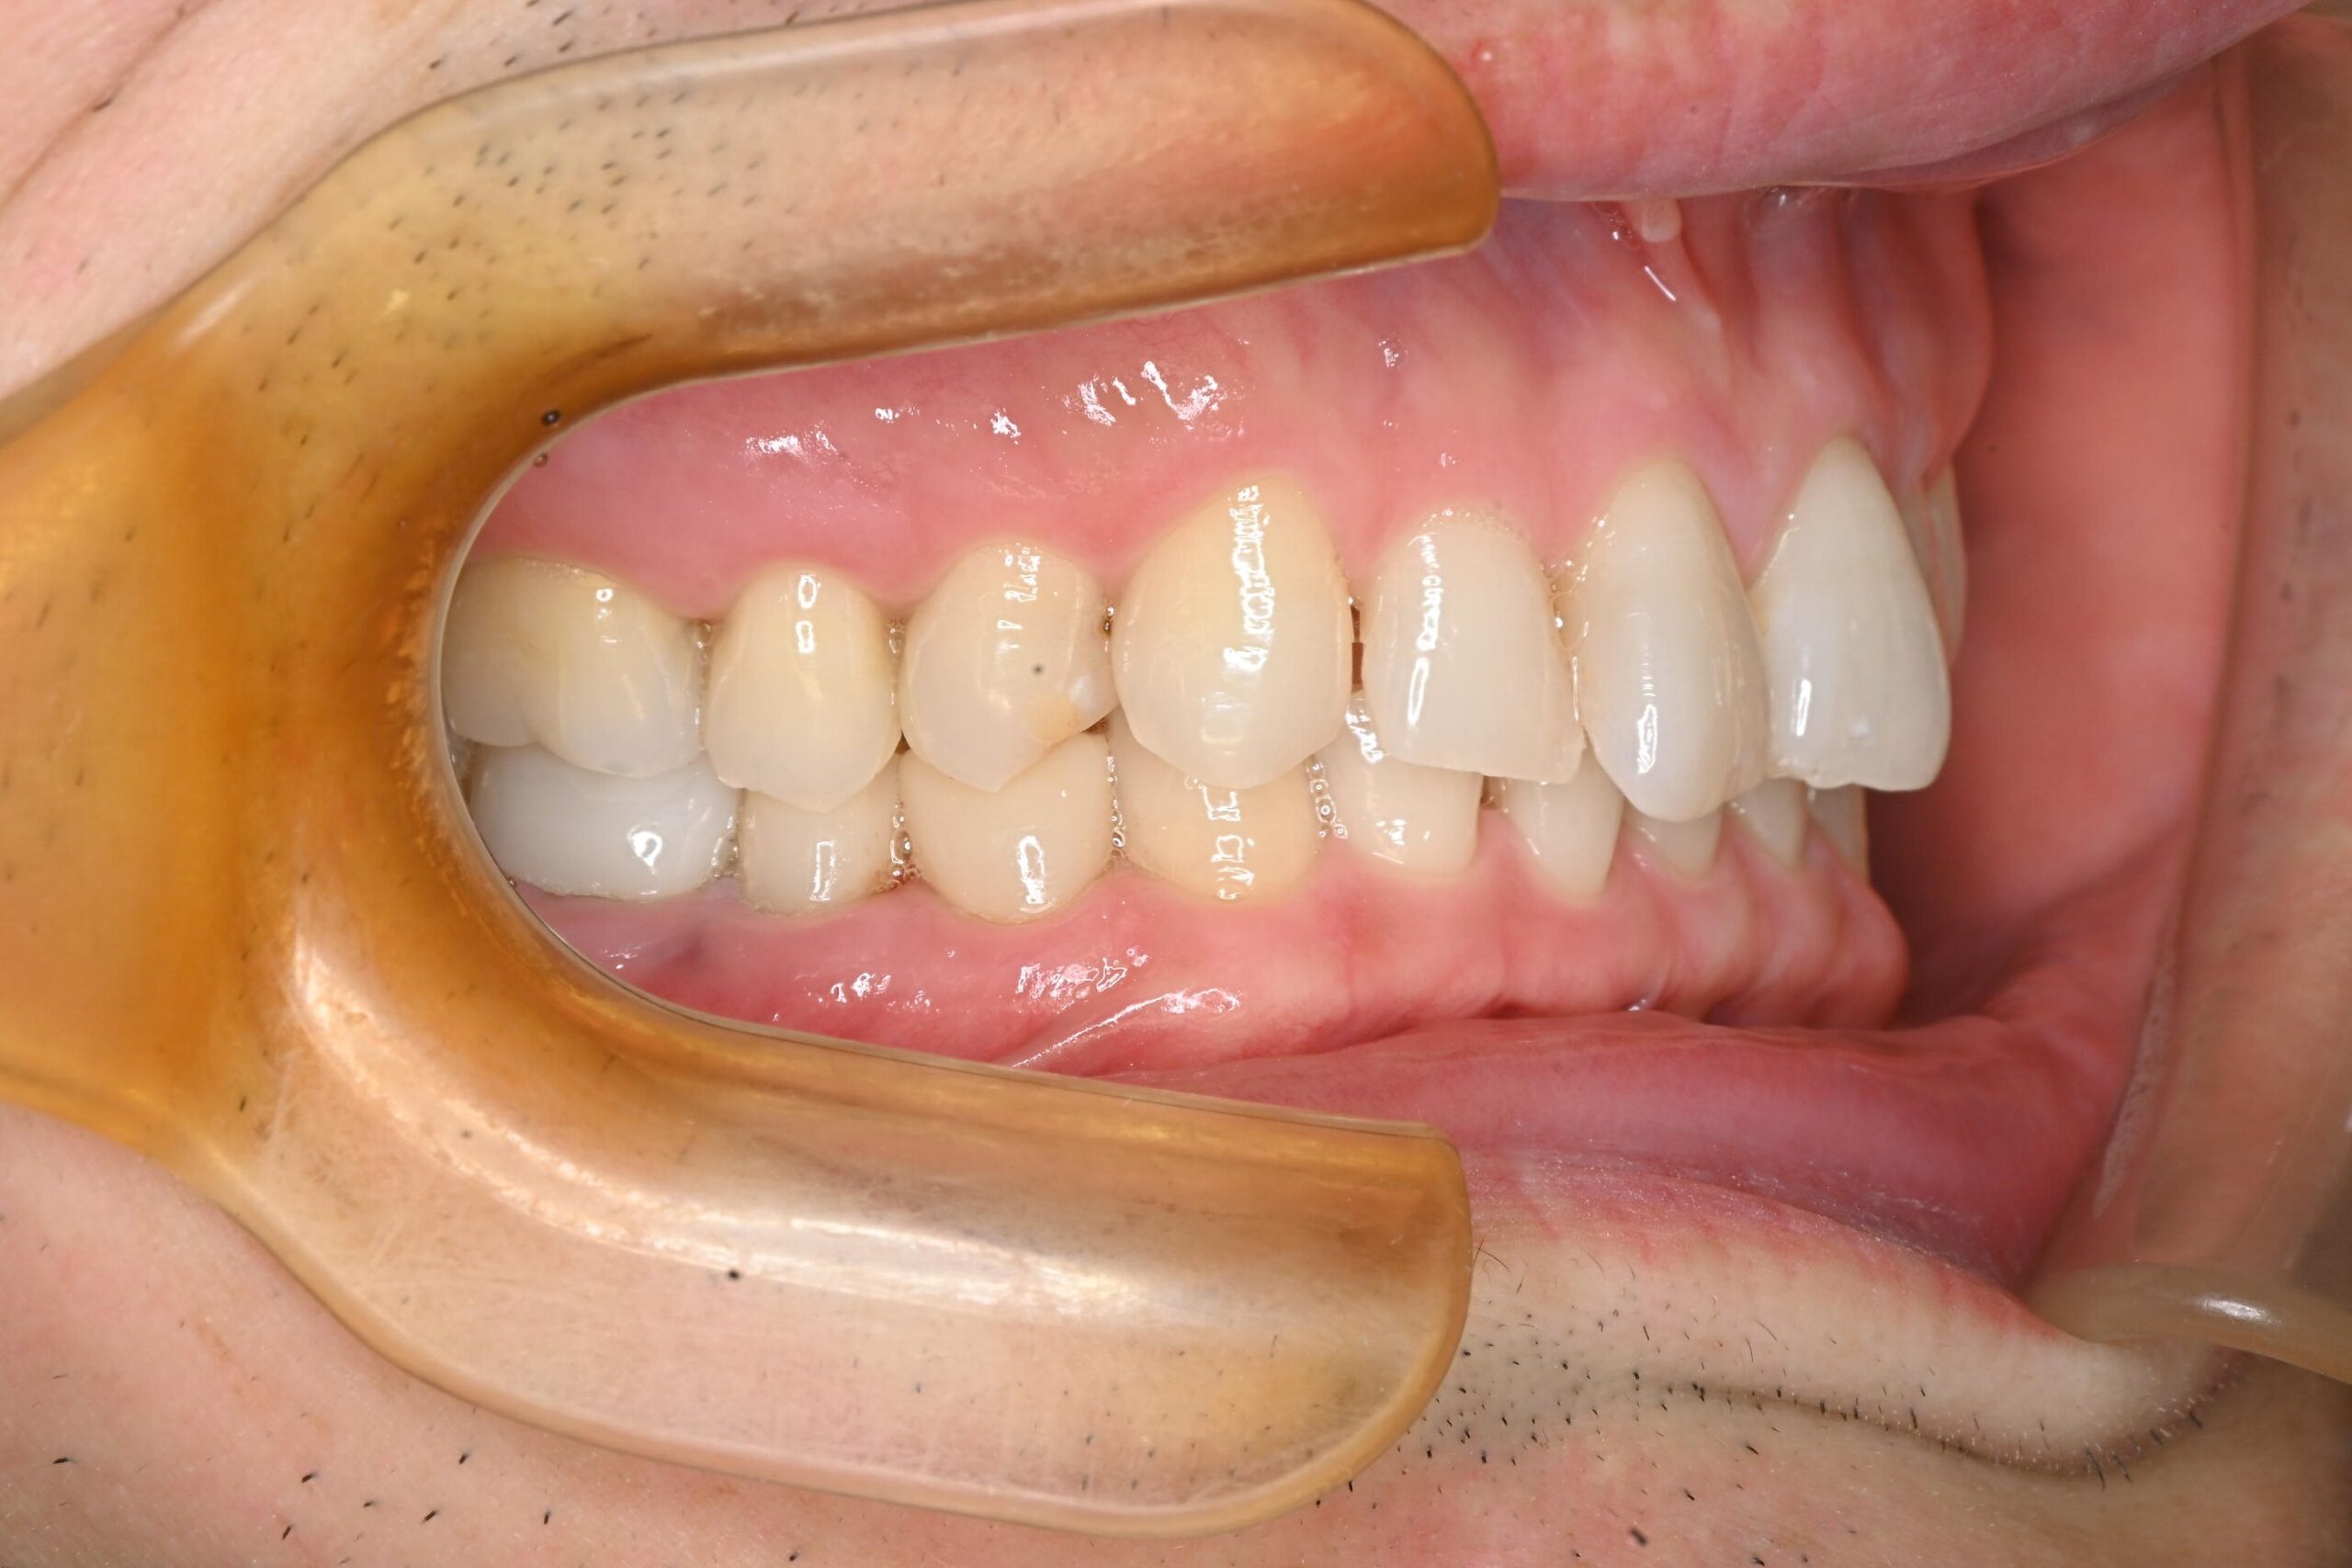

笑うと見える小臼歯(4番、5番)と大臼歯(6番)については、見た目の良い白い素材を使用しました。

• 強度重視(ジルコニア):

特に強度がかかる大臼歯(6番)については、硬く強度の高いセラミック素材であるジルコニアを選択しました。

• コストダウンと審美性の両立(プラスチック/PMMA):

比較的、窩洞が浅くて小さい小臼歯(4番、5番)については、コストダウンのご要望もあったため、保険ベースのプラスチック/PMMA素材で詰め物をしました。

ジルコニアとプラスチックを比べた場合、光の屈折率はプラスチックのほうが天然の歯と近く、色味はナチュラルになりやすいという利点があります。

しかし、強度の面では、プラスチックは天然歯の約1/5程度の強度しかないため、奥歯など力がかかる部分については破折のリスクを考え強度を重視し、ジルコニアを選択しました。

治療方針としては、見えるところは審美性重視、奥の力がかかるところは強度重視という選択になっています。もし将来的にプラスチック/PMMAが割れてしまった場合は、セラミックやジルコニアへの切り替えをご提案しています。

After